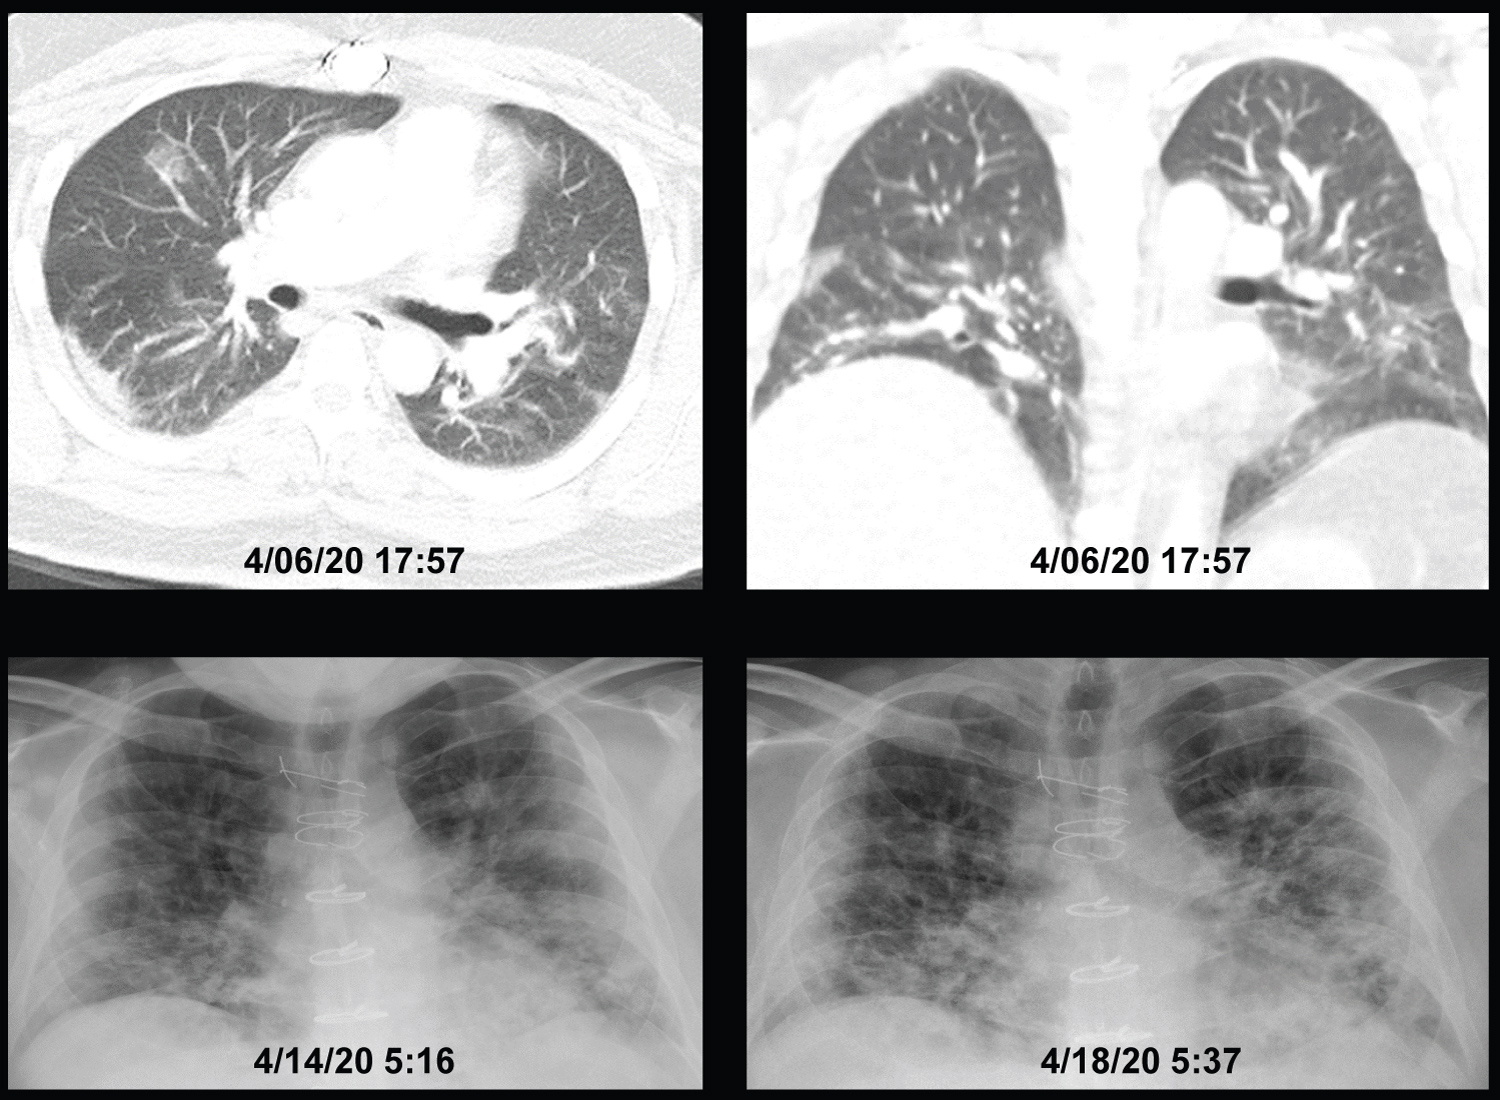

As shown on Table 1, their age ranged from 33 to 89-years-old and had multiple comorbidities associated with increased severity and mortality of COVID-19 [2]. They stayed in ICU between 3 and 14 days. Nine of 10 patients received oxygen through HFNC for most of their ICU stay with a median maximal flow rate of 50 l/min (IQR; 45, 60) and a median maximal inspired oxygen of 65% (IQR; 50, 80). One patient received BiPAP for a few hours followed by oxygen through nasal cannula. IL-6 was measured in 9 patients showing markedly elevated levels. All patients had the characteristic bilateral patchy ground glass lung opacities visualized in CT scans and/or chest-X-rays. Representative images from two patients with long ICU stays are shown in Figure 2 and Figure 3. All 10 patients gradually improved surviving the ICU stay and recovered. For comparison, we assessed the WOB scale in four patients with COVID-19 pneumonia who required intubation for mechanical ventilation. We compared the maximal and the average WOB scale (and its individual components) during the entire ICU stay for the 10 patients who did not require intubation and for the preceding 24 hours in the four patients who required intubation. As shown in Figure 4, there was a statistically significantly higher maximal and average WOB level in patients who require intubation. Breakdown of the various WOB components demonstrated a statistically significantly higher average but not maximal respiratory rate in patients who required intubation. Yet, the maximal and average use of respiratory accessory muscles use (assessed as their aggregate sum) was statistically significantly higher in patients who required intubation.

Figure 3: Patient #3, showing a CT of the chest 4 days before ICU admission and chest X-rays on ICU days 4 and 8. The patient spent 7 of 8 days in ICU receiving oxygen via high-flow nasal cannula between 50 l/min and 60 l/min and oxygen concentration between 50% and 65% during the initial 5 days and 50% for the last 2 days. His work of breathing averaged 3.5 (range 3-5) during the first 4 days improving gradually to an average of 2.5 (range 1-3) toward the end of his ICU stay without appreciable change in the chest X-ray. He was discharged from ICU once he was able to oxygenate adequately receiving oxygen through a simple nasal cannula without significant WOB increase at rest. View Figure 3